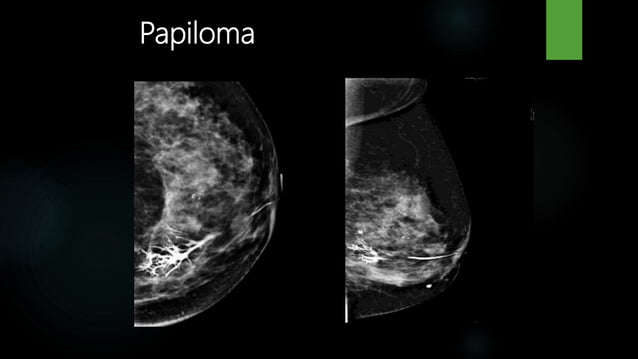

Causes for nipple discharge include duct ectasia, intraductal papilloma, and occasionally ductal carcinoma in situ or invasive ductal carcinoma.